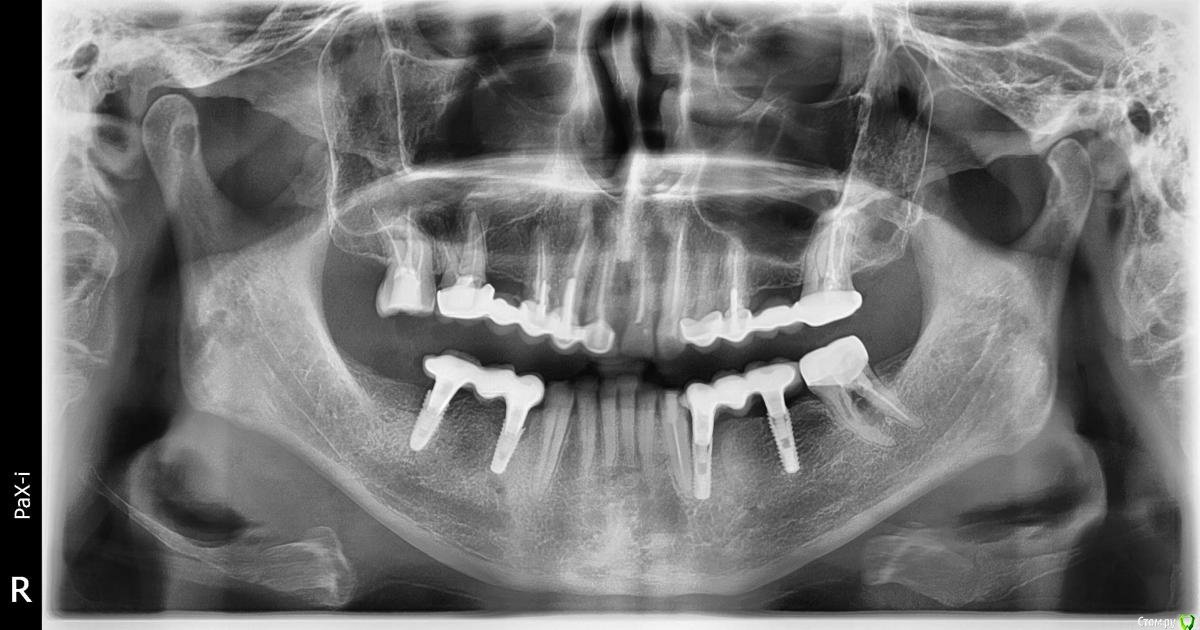

В апреле 2020 года была проведена имплантация на месте 34 и 36 зубов (корейская система INNO implant submerged 3.5x12, 4.0х12).

В июле 2020 года на импланты был установлен металлокерамический мост на приливаемых абатментах (винтовая фиксация). По состоянию на 20.11.2020 (4 месяца под нагрузкой) жалоб не было.

22.01.2020 ослабли винты на имплантах, был сделан новый снимок, где обнаружилось, что имплант на месте 36 сломался.

Снимки прилагаю.

post-62133-0-02490500-1611750764_thumb.jpg